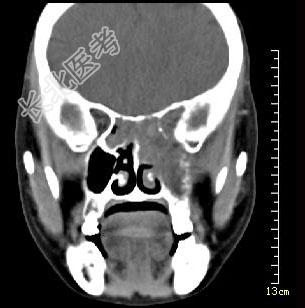

- 多项选择题男性50岁,涕中带血半年, 体检发现左侧颈部多个硬结,CT扫描如图所示, 请选择正确的描述和结论 ( )

A、左侧筛窦内见软组织块影,边缘不规则

B、软组织影累及对侧筛窦、左侧上颌窦

C、左侧眶内壁、上颌窦壁及颅底骨质破坏

D、考虑为左侧筛窦黏液性囊肿

E、考虑为左侧筛窦癌